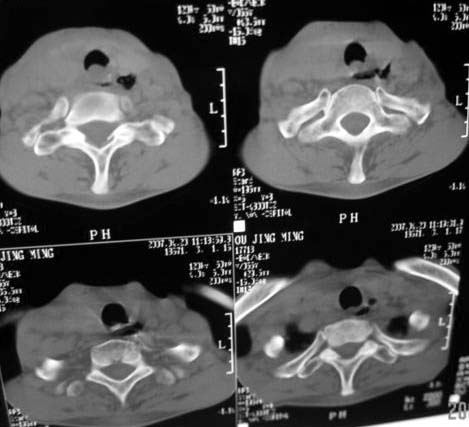

以下是引用dyqct在2007-4-20 16:19:00的发言:[br]考虑:1、左侧梨状窝区破裂伴左颈深、浅部气肿。[br] 2、右侧甲状腺区血肿(请追问病史是否伤及右颈部)。[br] 3、建议病情稳定后增强扫描除外右侧甲状腺腺瘤。